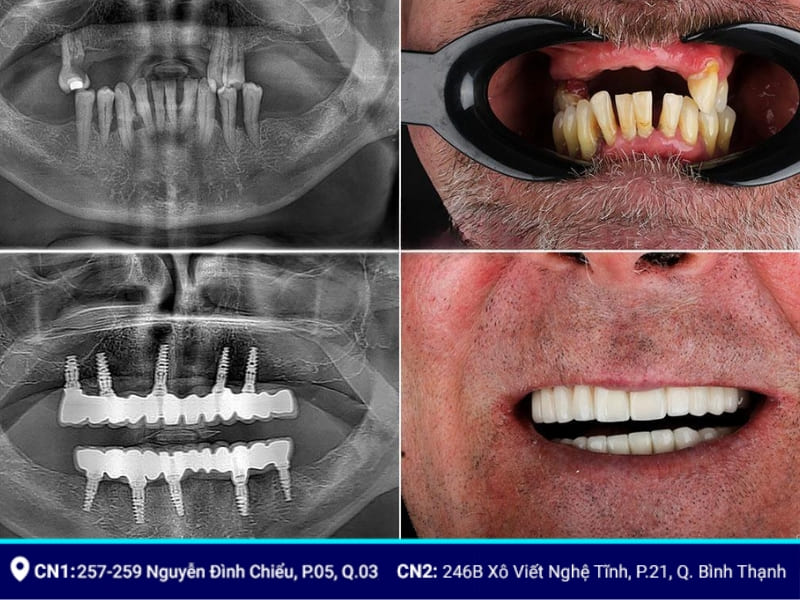

Cấy ghép Implant All-on-5 là một kỹ thuật phẫu thuật nha khoa tiên tiến, được đánh giá cao phục hình cho bệnh nhân mất nhiều răng. Với việc cố định 5 trụ Implant vào xương hàm, phương pháp này đảm bảo sự ổn định và phân bố lực nhai đều, tối ưu hóa quá trình tích hợp xương và tăng tuổi thọ của implant.

Đặc biệt, All on 5 còn ứng dụng công nghệ CAD/CAM trong thiết kế và chế tạo hàm giả, mang đến kết quả thẩm mỹ vượt trội, khôi phục chức năng ăn nhai và cải thiện chất lượng cuộc sống cho bạn.

Implant All On 5 là một trong những phương pháp trồng răng toàn hàm tiên tiến nhất hiện nay